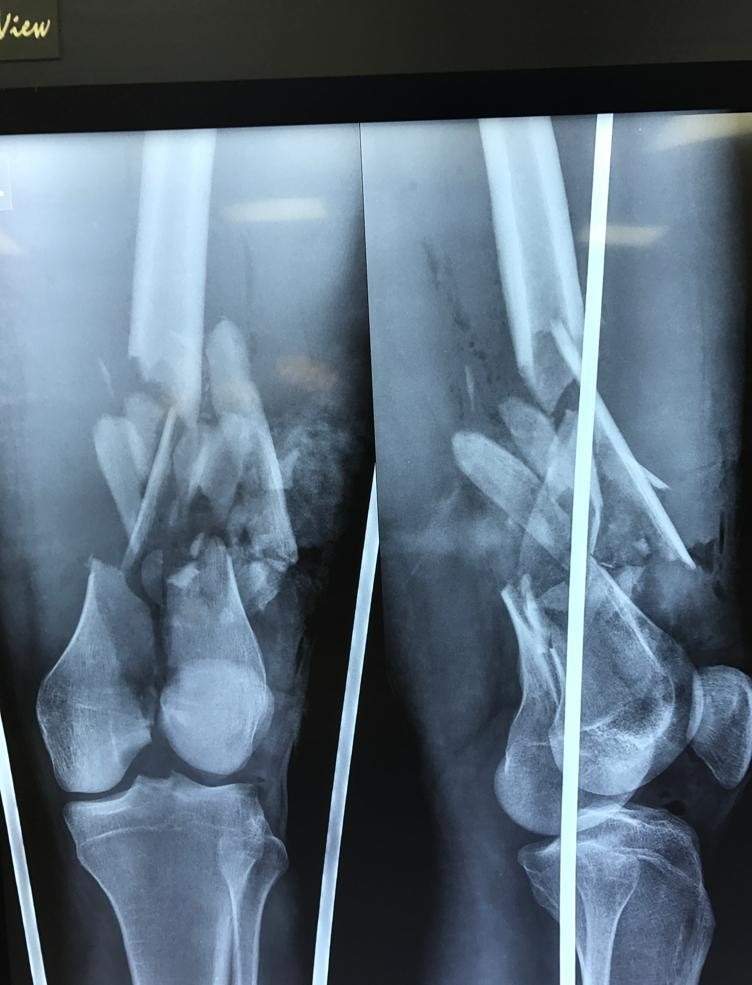

Pre Operative